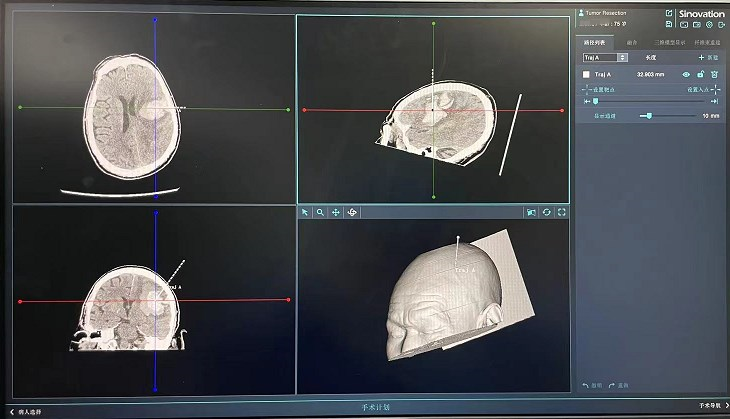

▲手术方案

▲导航引导下穿刺

神经外科高磊主任亲自进行手术风险评估及手术方案设计,于3月31日下午2点,在全身麻醉下为患者实施了导航下微创穿刺引流术,术后患者即刻清醒,可遵嘱配合简单指令动作。